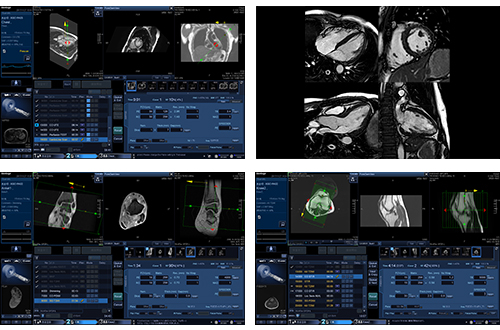

Интерфейс гентри переработан и отображает важную информацию о пациенте, чтобы оптимизировать рабочий процесс и сэкономить время настройки прибора.

На дисплеях демонстрируются все этапы обследования.

В сложных для разметки случаях поможет функция Auto Scan Assist. Она устраняет вариабельность и помогает автоматически разметить плоскости сканирования при исследовании головного мозга, позвоночника, коленных суставов и сердца.

ForeSee View – новый интеллектуальный инструмент планирования исследования, который позволяет просматривать срезы в реальном времени. Функция уменьшает необходимость повторного сканирования и экономит время на планирование исследования. Особенно полезна для диагностики анатомических областей, разметка которых затруднена, например, поджелудочной железы, сердца, суставов, извитых сосудов и связкок.

ForeSee View